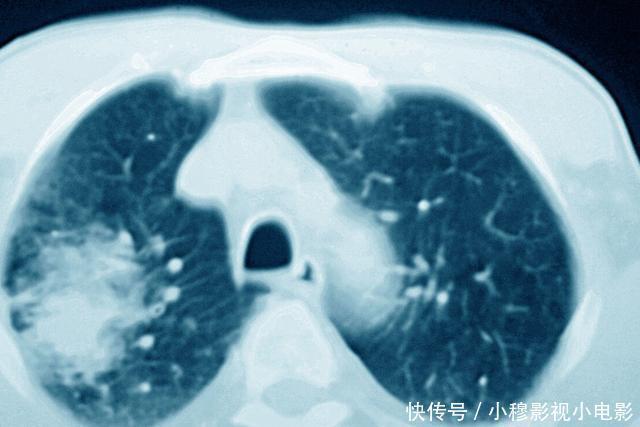

作用三:对某些癌症,可以评估治疗效果。

对于有的癌症,CT还能够起到评估治疗效果的作用;有的癌症患者,在发现的时候已经没有了手术治疗的机会;也有的癌症,本身就不适合手术治疗,这个时候可能就需要放化疗等其他的治疗方法来治疗癌症。那么对于这些治疗方法,往往评估疗效非常重要的办法就是进行CT检查。

比如淋巴瘤,大部分淋巴瘤患者都是没有办法进行手术切除的,主要的治疗方法是化疗和放疗。而在进行化疗之后,医生需要判断化疗的效果,这个时候往往就需要结合CT检查,通过CT检查,了解病灶有没有缩小、减少,如果病灶出现了缩小、减少,那么说明治疗有效果,而如果复查病灶没有明显的变化,那么则说明化疗效果不佳,可能需要调整治疗方案。

另外,有的癌症可能一开始没有办法手术,但是可以先通过放化疗,把病灶缩小,然后再进行手术治疗,那么这其中也是需要通过CT检查来评估病灶情况,了解是否可以手术。